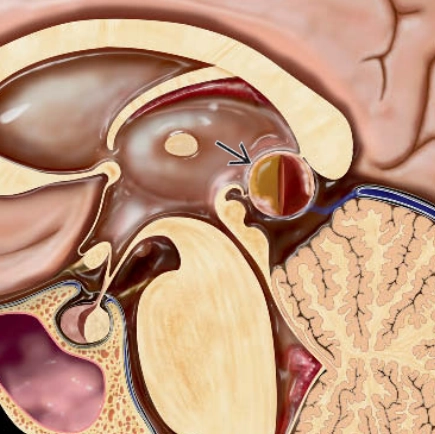

U thần kinh đệm dạng dây của não thất 3 (Chordoid Glioma of the 3rd Ventricle - CGOTV)

16/03/2026